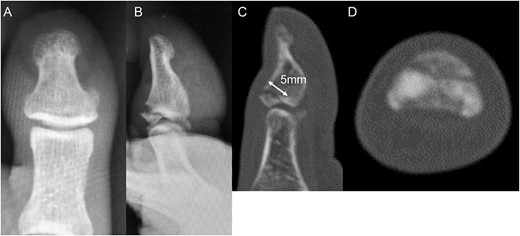

A 54-year-old man injured his right great toe while walking and wearing sandals. He complained of tenderness, swelling, and pain during motion. He could bear weight but could not actively extend the interphalangeal (IP) joint of the hallux. He was referred to our outpatient clinic 3 days after the injury. Physical examination revealed swelling, tenderness, and motion pain, and the patient could not extend the IP joint of the hallux. Plain lateral radiography and computed tomography revealed a displaced avulsion fracture of the dorsal base of the distal phalanx (Fig. 1). Surgery was performed under general anesthesia after informed consent was obtained on posttraumatic day 11. A Y-shaped incision was made at the center of the dorsal IP joint, and the displaced bony fragment was attached to the extensor hallucis longus (EHL). The IP joint was temporarily fixed with a 1.6 mm Kirschner wire, and the fragment was repositioned and fixed with two 1.5 mm cortical screws (APTUS® Hand, Medartis, Basel, Switzerland). A 4-0 FiberWire® (Arthrex, Naples, FL, USA) was fastened as an augmentation proximally to the EHL tendon and distally to the periosteum of the distal phalanx in a figure eight (Fig. 2). Postoperatively, the ankle was externally fixed in dorsiflexion from the leg to the toe, and heel loading was permitted. A total of 4 weeks after surgery, the Kirschner wire was removed to allow active motion of the IP joint of the hallux, and weight bearing was allowed on the hallux 5 weeks postoperatively. Plain radiographs taken 3 months after surgery confirmed bone healing (Fig. 3). A total of 20 months postoperatively, the patient acquired normal function, and the range of motion of the affected IP joint ranged from −3° to 30°, with no difference from the unaffected side (Fig. 4). Skin necrosis or nail deformities were not observed.

Plain radiographs (A) anterior–posterior view and (B) lateral view show an avulsion fracture of the dorsal base of the distal phalanx. Plain computed tomography (C) sagittal slice and (D) axial slice reveals an avulsion fracture of the dorsal base of the distal phalanx similar to the plain radiograph. Additionally, the fracture length line of the fragment was 5 mm.